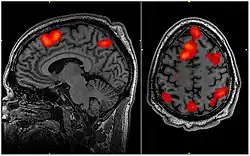

Funkční magnetická rezonance (fMRI) je moderní zobrazovací metoda sloužící k funkčnímu zobrazování mozku, resp. mapování mozkové odezvy na vnější či vnitřní podnět. S vývojem výpočetní techniky a statistických metod se rozvíjí metoda fMRI jako nástroj pro vizualizaci anatomických struktur mozku zapojených do mechanismů vnímání, řízení motoriky a myšlení. Liší se od standardní magnetické rezonance schopností detekovat dynamické změny signálu způsobené lokálním kolísáním poměru oxyhemoglobinu a deoxyhemobloginu v závislosti na neuronální aktivitě (BOLD, tzn. Blood Oxygenation Level Dependent).

fMRI mapuje neuronální aktivitu pouze nepřímo, v návaznosti na lokální změnu oxygenace a perfuze mozkové kůry. Z toho také vychází její přednosti a limitace ve srovnání s dalšími metodami funkčního mapování mozku. Meze jednotlivých metod jsou dány tzv. časovou a prostorovou rozlišovací schopností. Funkční MRI má relativně vysokou prostorovou rozlišovací schopnost (řád jednotek milimetrů), časová rozlišovací schopnost je ve srovnání s EEG (elektroencefalografie) či MEG (magnetoencefalografie) omezená. fMRI nalézá uplatnění především v neurofyziologickém výzkumu. Na řadě pracovišť se fMRI využívá např. jako doplňující vyšetření před neurochirurgickou intervencí v oblastech kritických pro řečové či motorické funkce. fMRI umožňuje zpřesnění diagnostiky některých neurologických i psychiatrických onemocnění a nabízí možnosti plánování chirurgických výkonů.

K funkčnímu mapování mozkové kůry pomocí MR je možno užít dvou principů. Jedná se buď o změnu perfuze a objemu krve v místě neuronální aktivity (perfuzní fMRI), anebo navíc o změnu poměru okysličené a neokysličené formy hemoglobinu v dané oblasti (BOLD fMRI).

Podstatou metody je změna prokrvení a objemu krve v aktivní oblasti mozkové kůry (perfuzní fMRI) nebo změna mezi poměrem okysličené formy hemoglobinu (BOLD fMRI). Neokysličená forma hemoglobinu má paramagnetické vlastnosti a chová se jako přirozená MR kontrastní látka, která zkracuje relaxační čas T2. Aktivní oblast mozku, která spotřebovává více kyslíku, potom poskytuje silnější signál než okolí. Při fMRI vyšetření se opakovaným skenováním získávají obrazy celého objemu mozku v klidu i při aktivním řešení úkolů (reakce na podnět, pohyb končetin, tvorba slov, atd.) Změny mozkové aktivity jsou měřeny z rozdílu dvojic obrazů podřízených v klidu a při mozkové činnosti.

Výsledek voxel-by-voxel detekční metody získáváme statistickou parametrickou mapu (SPM= statistical parametric map). Po provedení prahování (pro každý bod musí být rozhodnuto o významnosti či nevýznamnosti statistické hodnoty) mapy, je získána výsledná mapu detekovaných aktivací a používá se k hodnocení výsledku experimentu.[1]